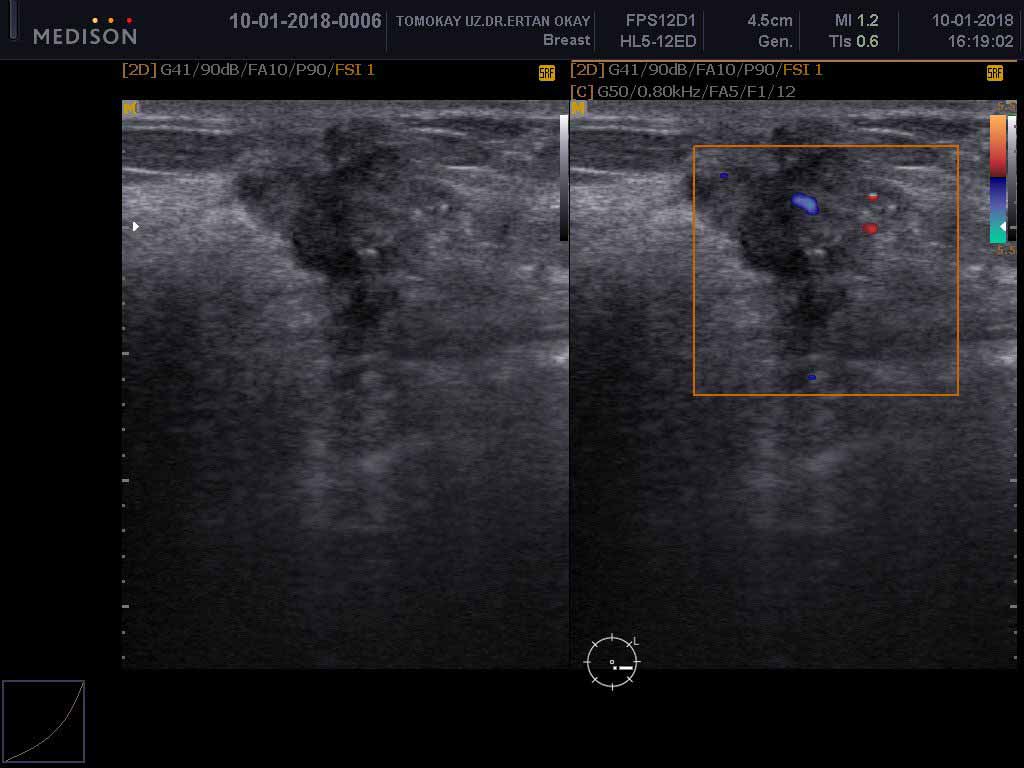

الموجات فوق الصوتية للثدي